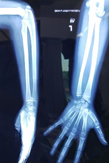

Case-V

53 years, male;

Comminuted fracture mid shaft of Radius & Ulna (Figure 18-21).

Figure 18 Pre-operative x-ray.

Figure 19 Follow up x-ray DCP fixation with infection.

Figure 20 X-ray after Ilizaro Osteo-synthesis.

Figure 21 X-ray after union.